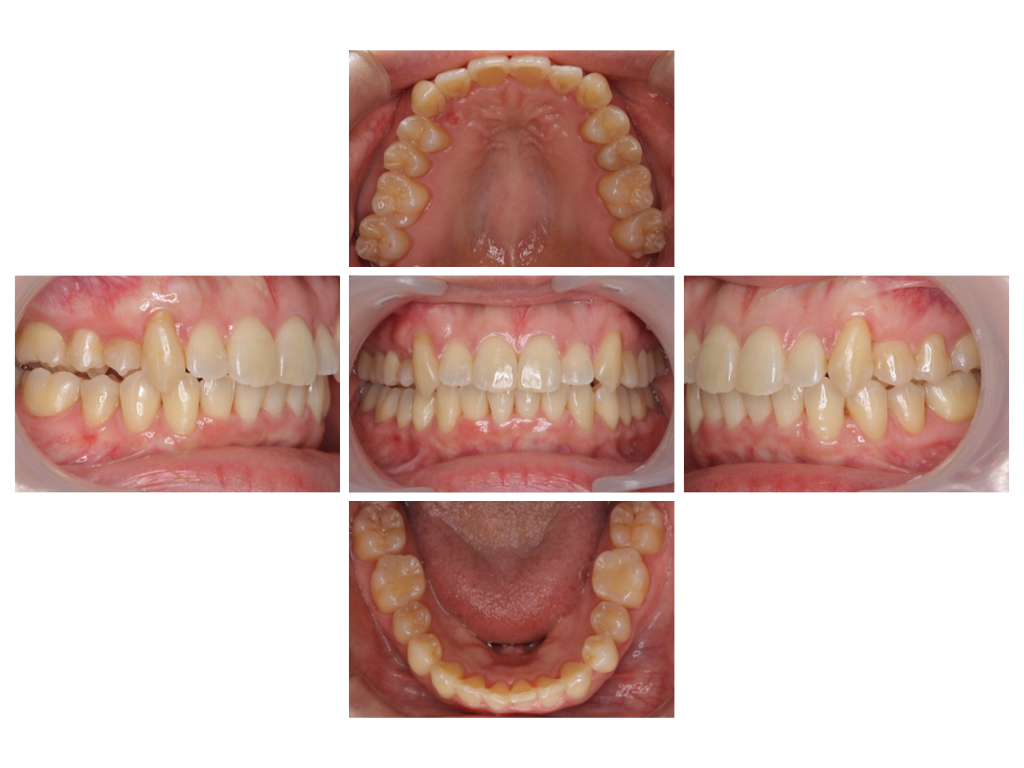

before

40代/女性 歯のガタガタが気になる

期間 ➖ 4年6か月

費用 ➖ 880,000円(税込・調整料込)

治療内容 ➖ 歯並びがデコボコしていたため、顎の横幅を広げてスペースを作り、きれいに並べました。

前歯が前に出ないように、噛み合わせのバランスを整えながら治療を進め、上下の真ん中の位置(正中)も揃えました。